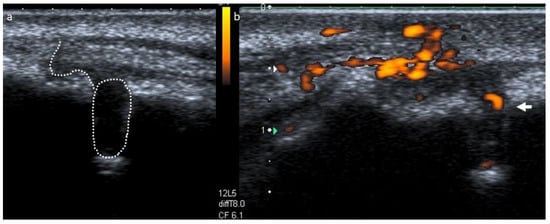

2. Case Report